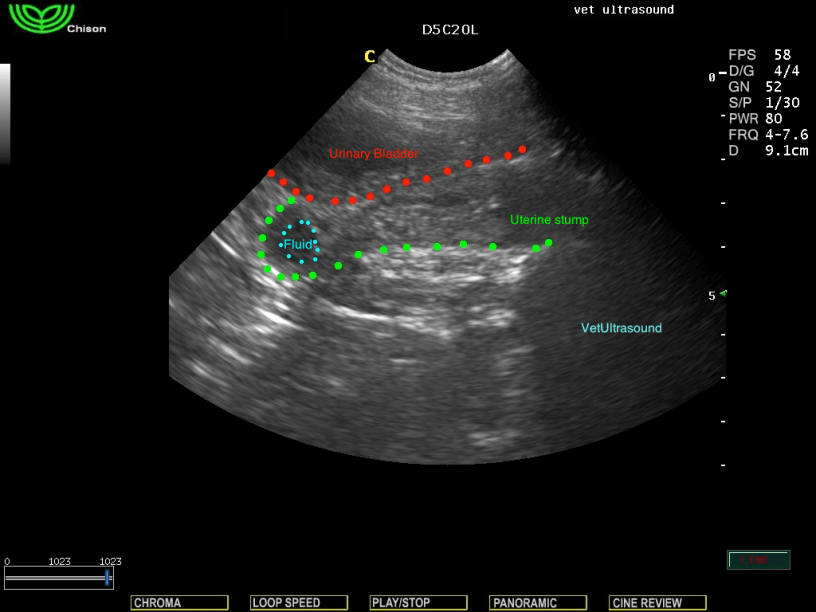

Ευρήματα: Στον υπέρηχο βρέθηκε παρουσία μικρής ποσότητας υγρού στο κολόβωμα της μήτρας και πάχυνση του τοιχώματός του. Στην δεξιά περιοχή πίσω από τον νεφρό ελέγχθηκε κυστική αλλοίωση η οποία αντιπροσώπευε την δεξιά ωοθήκη

(υπόλειμμα).

Διάγνωση: Εικόνα αρχικού σταδίου πυομήτρας του κολοβώματος.